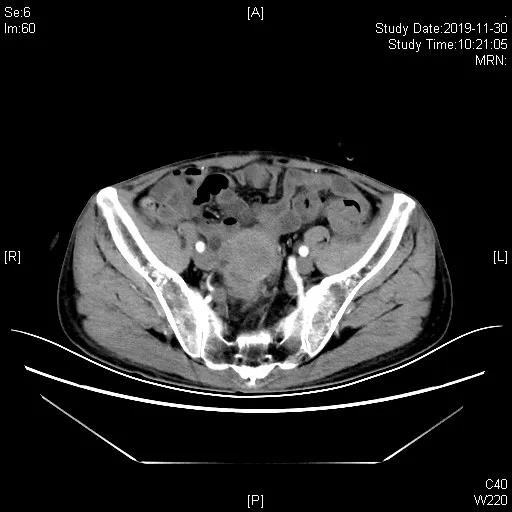

一线治疗:2019-05-21 “吉西他滨1.2d1,d8+卡铂500mgd2”化疗1周期,06-17 “吉西他滨1.4d1,d9+奥沙利铂200mgd2”化疗1周期。07-12胸腹部CT及盆腔MRI评估近期疗效为完全缓解(CR)。于07-12至10-05共计“吉西他滨1.4d1,1.2d14+奥沙利铂200mgd2”化疗4周期,III°血小板减少及白细胞减少,影像学评估CR。11月底出现造瘘口出血, 11-30胸腹部CT示回肠代膀胱壁增厚伴软组织肿块,考虑再次复发。

一线化疗6周期结束后40天评估,评估PD